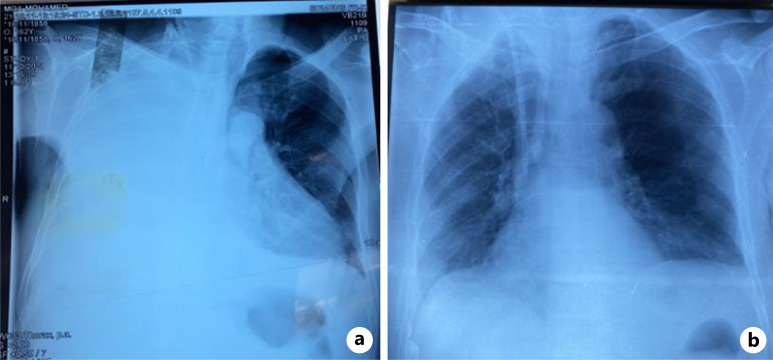

Introduction: Pleuroperitoneal leakage is a rare but dramatical cause of pleural effusion; it can lead to the cessation of peritoneal dialysis. It typically manifests as respiratory distress and reduced drainage volumes.

Case presentation: In this article, we report a case of pleuroperitoneal leak in a patient undergoing continuous ambulatory peritoneal dialysis who presented to the emergency with shortness of breath, lower limb edema, and weight gain. The diagnosis was established through pleural puncture, revealing that the pleural fluid is transudative with elevated glucose level which is pathognomonic for this condition, "sweet hydrothorax." Furthermore, the composition of this fluid was almost identical to the peritoneal dialysis effluent. The management of this case involved temporarily discontinuing peritoneal dialysis and performing pleurodesis. The evolution was favorable, and peritoneal dialysis was resumed 2 weeks later.

Conclusion: Patients on peritoneal dialysis who present with significant pleural effusion, especially if it is unilateral, should prompt clinicians to consider the possibility of a pleuroperitoneal leak.